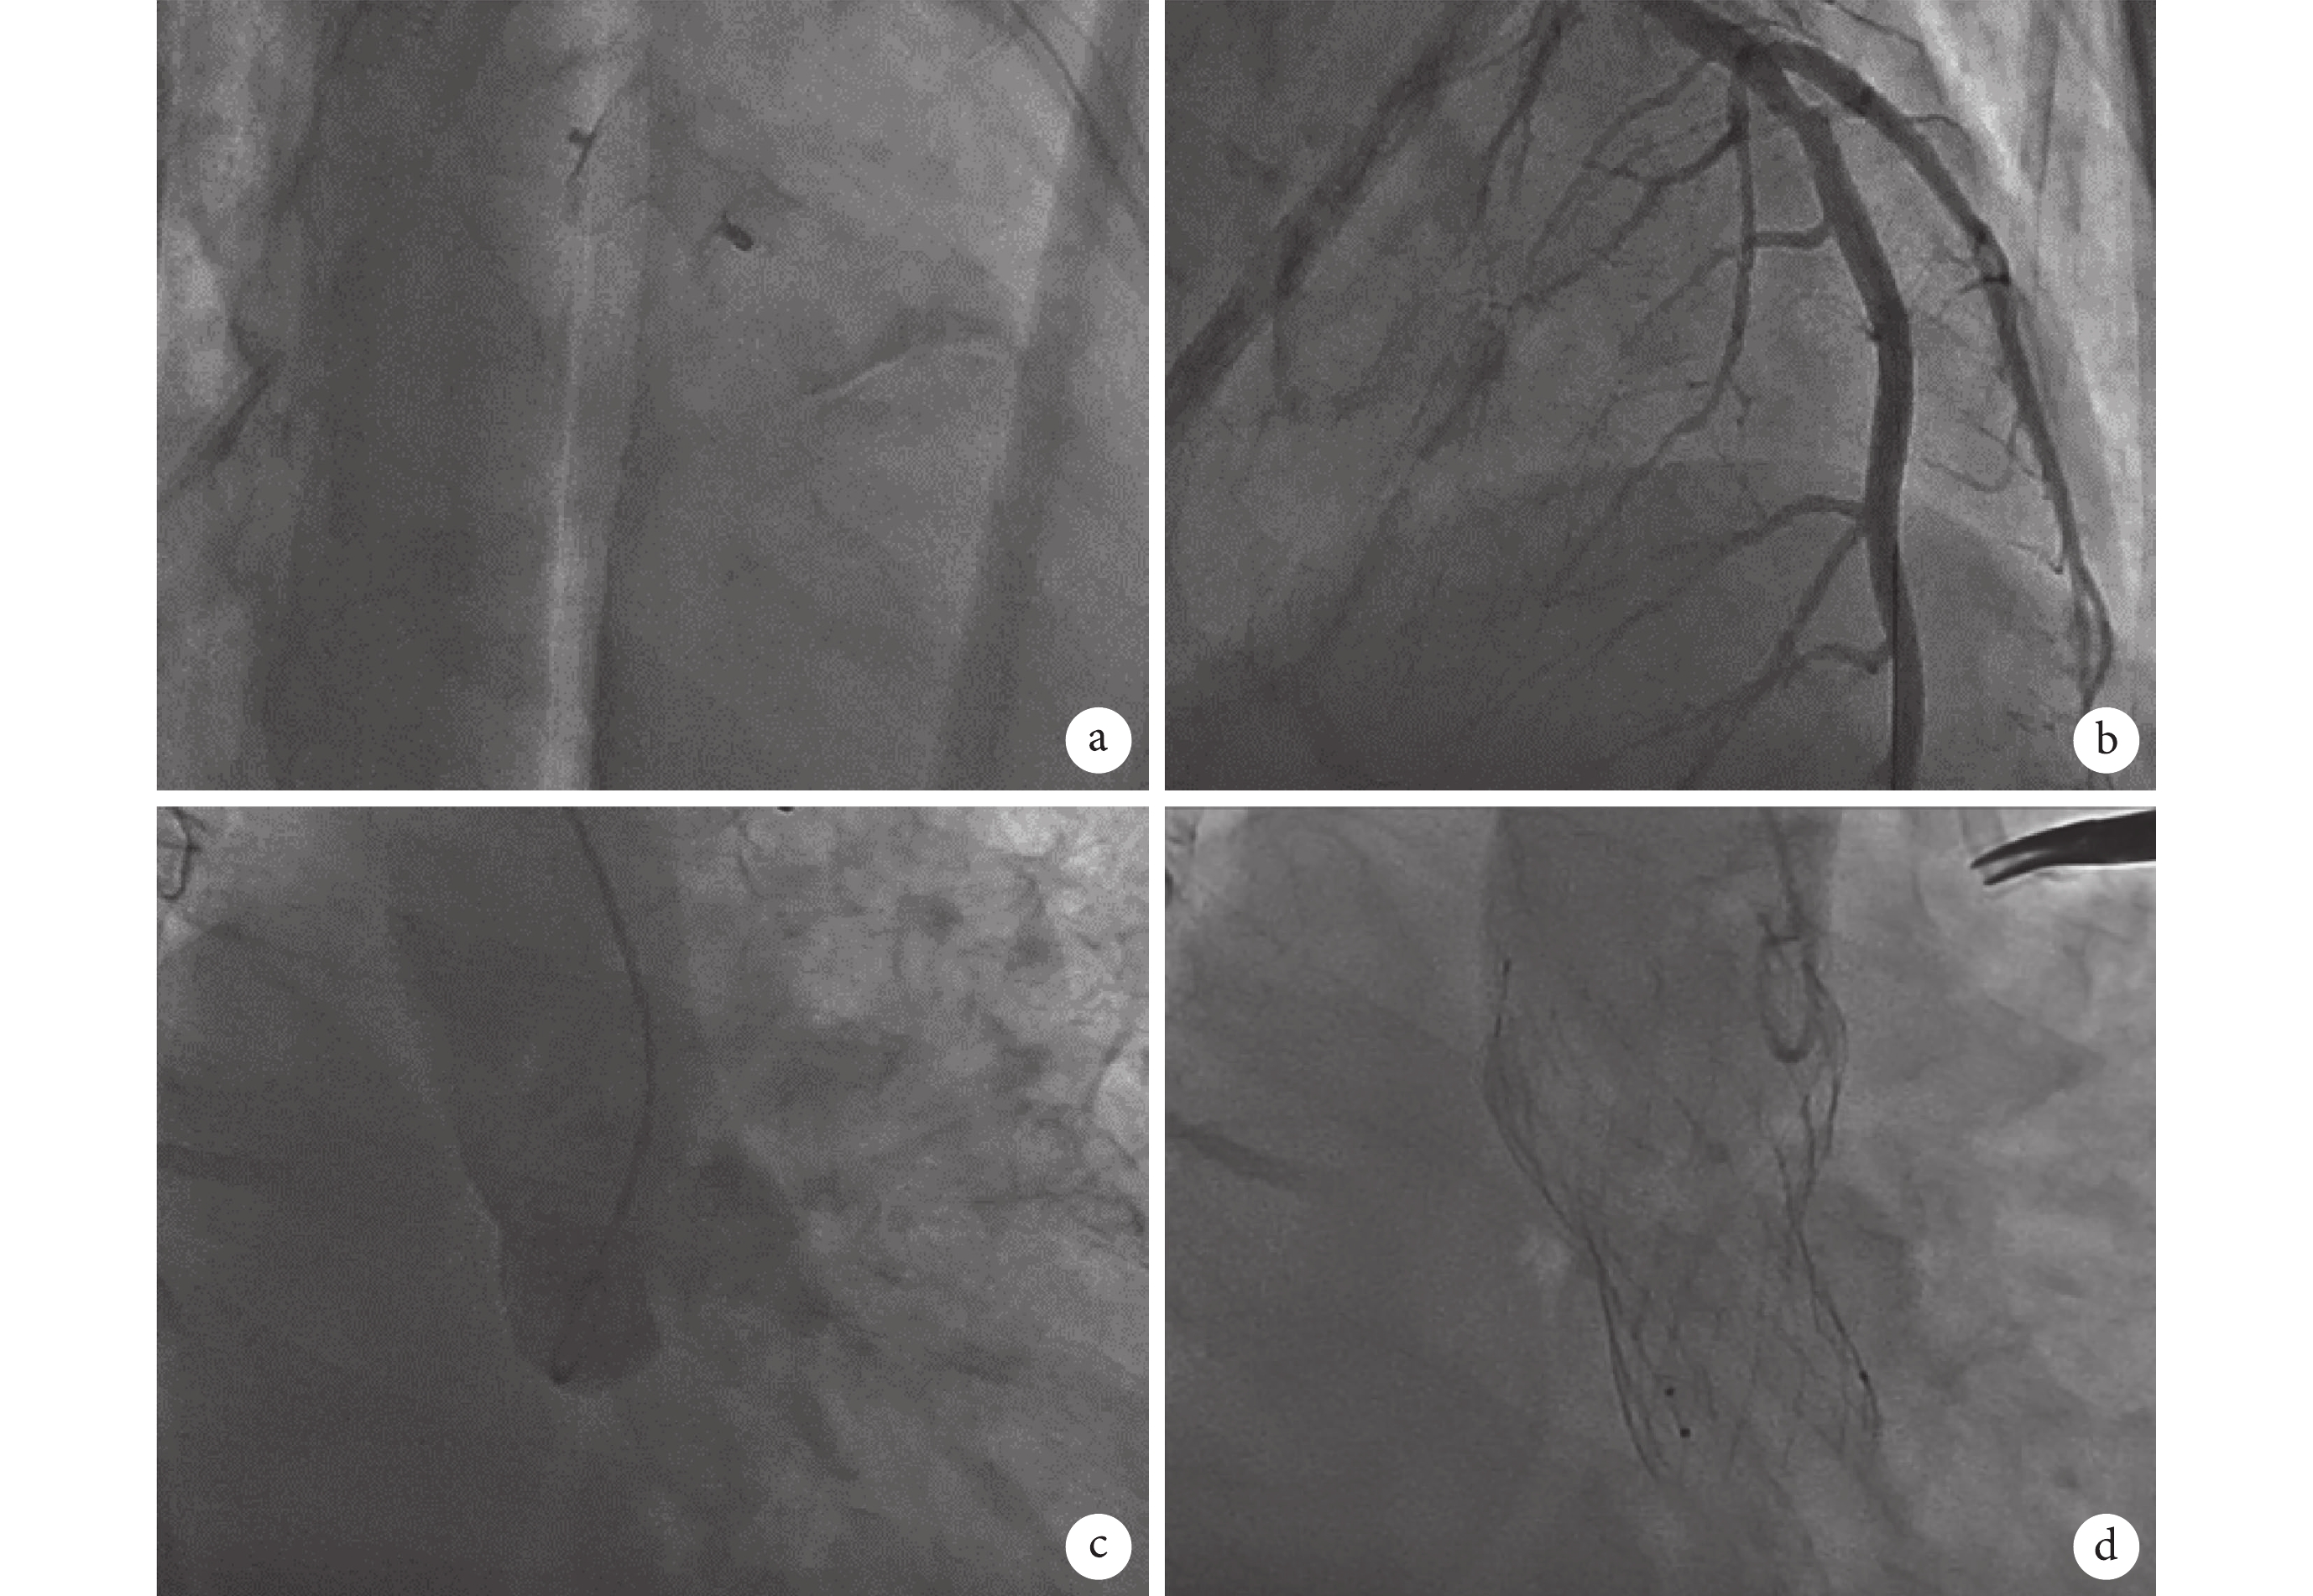

a. PDA 封堵傘置入;b. PCI 術后冠狀動脈造影;c. TAVR 術前主動脈根部造影;d. TAVR 術后主動脈根部造影

手術過程:患者急性心力衰竭入雜交手術室,呈休克狀態(血壓 65/33 mm Hg),肝腎功能衰竭、無尿、靜脈壓高,麻醉成功后,患者取仰臥位,常規消毒鋪單,肝素化 3 mg/kg,行左股動、靜脈插管,連接體外循環機備用。行 PDA 封堵術,自右股靜脈穿刺,送入 6F 端孔導管,沿右心房-三尖瓣-右心室-肺動脈-動脈導管進入降主動脈后,交換超硬導絲,沿超硬導絲置入輸送鞘管至降主動脈,撤出導絲及內套管,連接裝有國產華醫圣杰 14/16# 動脈導管封堵器裝載器,推送至降主動脈,以左側 90° 角度透視下釋放封堵器,回拉完全釋放封堵器,閉合動脈導管,反復拉動傳送桿,封堵器位置牢固,術中超聲示形態良好,釋放封堵器,封堵成功,撤出傳送桿及鞘管(圖2a)。行冠狀動脈造影術,自右橈動脈穿刺,以 5F 造影導管行左、右冠狀動脈造影。冠狀動脈造影顯示:冠狀動脈左優勢型,左主干未見狹窄;前降支彌漫鈣化、斑塊,中段對角支發出后 85% 狹窄,回旋支彌漫鈣化、斑塊,鈍緣支近段 50%~60% 狹窄;右冠狀動脈斑塊,未見明顯狹窄。行 PCI 術,送入 6F EBU3.5 導引導管到左冠狀動脈開口,應用 SION BLUE 導絲到達遠段,應用 2.5 mm×15 mm 球囊以 10 s 預擴病變處,于前降支近中段以 10 s 植入一枚 3.5 mm×18 mm 愛立藥物支架,術后沿導絲送入 2.75 mm×15 mm 耐高壓球囊至支架內以 10 s 加壓后擴。重復造影見前降支支架植入部位無殘余狹窄,無夾層和邊支閉塞(圖2b)。行 TAVR 術,自右橈動脈置標記導管并行主動脈根部造影(圖2c)。自右股動脈置入右心室起搏導管。左頸部取縱切口,約 5 cm,游離左頸動脈并繞帶,穿刺置入 10F 動脈鞘,沿右側 10F 股動脈鞘送入 5F AL1 導管至升主動脈,交換直頭導絲跨主動脈瓣至左心室,將 AL1 導管沿導絲送至左心室,經 AL1 導管交換超硬導絲至左心室,撤出 AL1 導管;撤出 10F 血管鞘,沿超硬導絲置入 20F 導引鞘。選擇工作體位,沿超硬導絲置入 22 mm 球囊擴張管,在 180 次/min 的超速起搏下,22 mm 球囊擴張并造影,膨脹良好無反流,患者心室顫動,血壓進行性下降,除顫一次,心臟復跳,循環恢復。撤出球囊,沿超硬導絲置入 Venus-A Plus 輸送系統,在 200 次/min 的超速起搏下,標準位置入啟明 Venus-A 29 mm 介入瓣膜支架一枚,置入瓣膜定位良好,行主動脈根部造影,見瓣膜開放良好,未影響冠狀動脈開口,輕度瓣周反流,遂以 22 mm 球囊在 180 次/min 的超速起搏下后擴一次,行主動脈根部造影,見瓣膜開放良好,未影響冠狀動脈開口,舒張期幾無反流(圖2d),經胸超聲心動圖顯示瓣膜啟閉良好,幾無反流。患者血壓 108/59 mm Hg,撤出置入系統及導絲,縫合血管切口,檢查無出血,縫合皮膚切口,術畢,安返重癥監護病房,給予心外科特級護理、呼吸機輔助呼吸、抗感染、營養心肌等綜合治療。